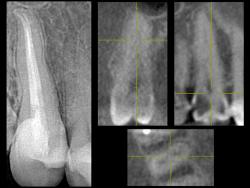

• Горизонтальные срезы через устьевую часть и среднюю треть:

щелевидный вход и 2 корневых канала (рис. 57-60).

• Корневые каналы 1.5 зуба обработаны УЗ инструментами, форма придана вращающимися NiTi файлами Protaper (рис. 61).

| Рис. 57-58 Горизонтальный срез через устьевую часть 1.5 зуба; выделенные фрагменты и 3-D визуализация (3-D Interactive Tooth ATLAS): щелевидный профиль корневого канала |

| Рис. 59-60 Горизонтальный срез через устьевую и среднюю треть 1.5 зуба; выделенные фрагменты и 3-D визуализация: два устья |